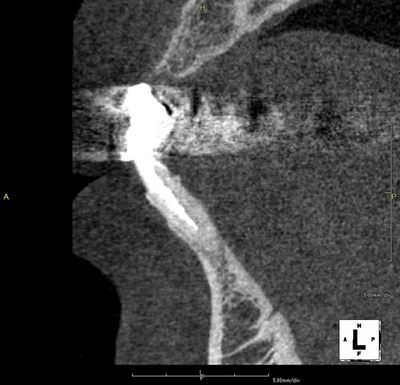

左下中切歯の再根管治療を行います。(矢印)

歯科用CTによる立体画像です。

白く棒状に写っているのがガッタパーチャ(根管充填材)です。

同じく治療前の断面図です。

根尖(歯根の先端)までの攻略・充填を目指します。